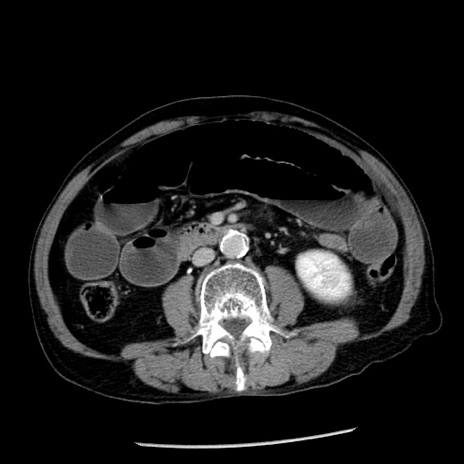

冠状断像

【症例】80歳代男性

【主訴】嘔吐

【現病歴】昨晩2回嘔吐あり、今朝になっても嘔吐あり。来院。

【既往歴】胃潰瘍

【身体所見】意識清明、BT 37.6℃、BP 166/95mmHg、HR 100bpm、SpO2 97%、腹部:平坦・軟、腸蠕動音聴取良好、圧痛なし。

【データ】WBC 21900、CRP 1.46